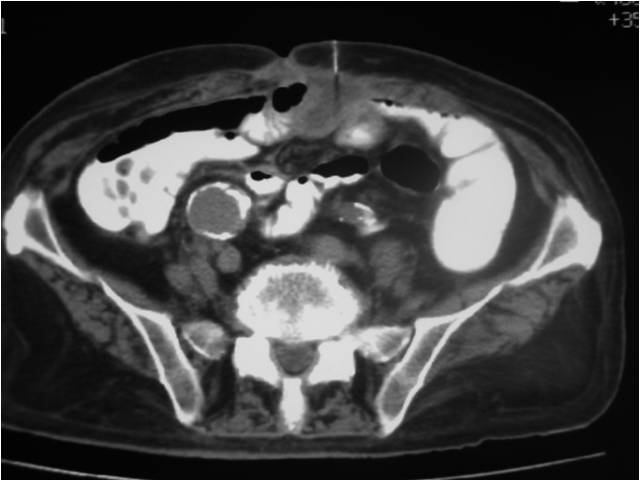

- Abscess post right hemicolectomy

- Successful placement and drainage